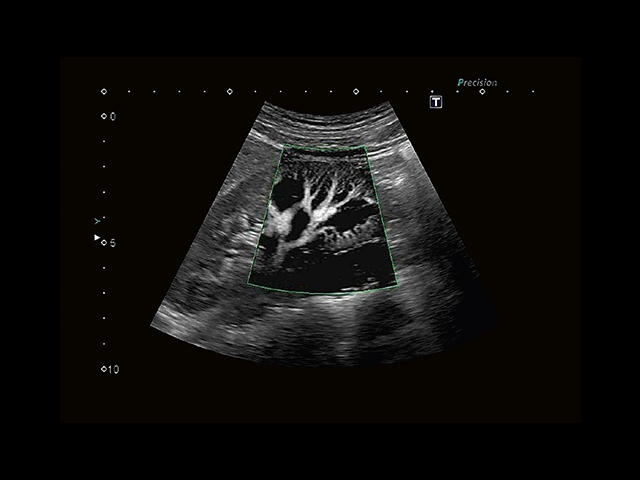

Обновленная версия легендарного УЗ-сканера. Стационарный аппарат экспертного класса Aplio 500 Toshiba NEW, визуализирует анатомические структуры в высоком разрешении. Модель позволяет выявить микрокальцификаты, новообразования, нарушения в работе сердца, сосудов и мышц. Присутствует функция виртуальной эндоскопии, 4D-сканирования, эластометрии тканей, УЗИ с контрастированием. За повышение качества изображения отвечают технологии ApliPure и Superb Microvascular Imaging. Первая задействует возможности пространственного и частотного кодирования, формирует цельный визуальный ряд с сохранением клинических маркеров. Вторая улучшает отображение микрососудистого русла, используя доплеровский эффект. Модель оснащена 21-дюймовым монитором, имеет 4 активных порта. Возможно подключение педиатрических, интраоперационных, лапароскопических и чреспищеводных датчиков.

• MicroPure. Высокотехнологичное решение в области выявления микрокальцификатов – маркеров новообразований злокачественного типа. Маркеры идентифицируются путем изучения затененных изображений целевого участка. Микрокальцификаты отображаются в виде белых пятен.